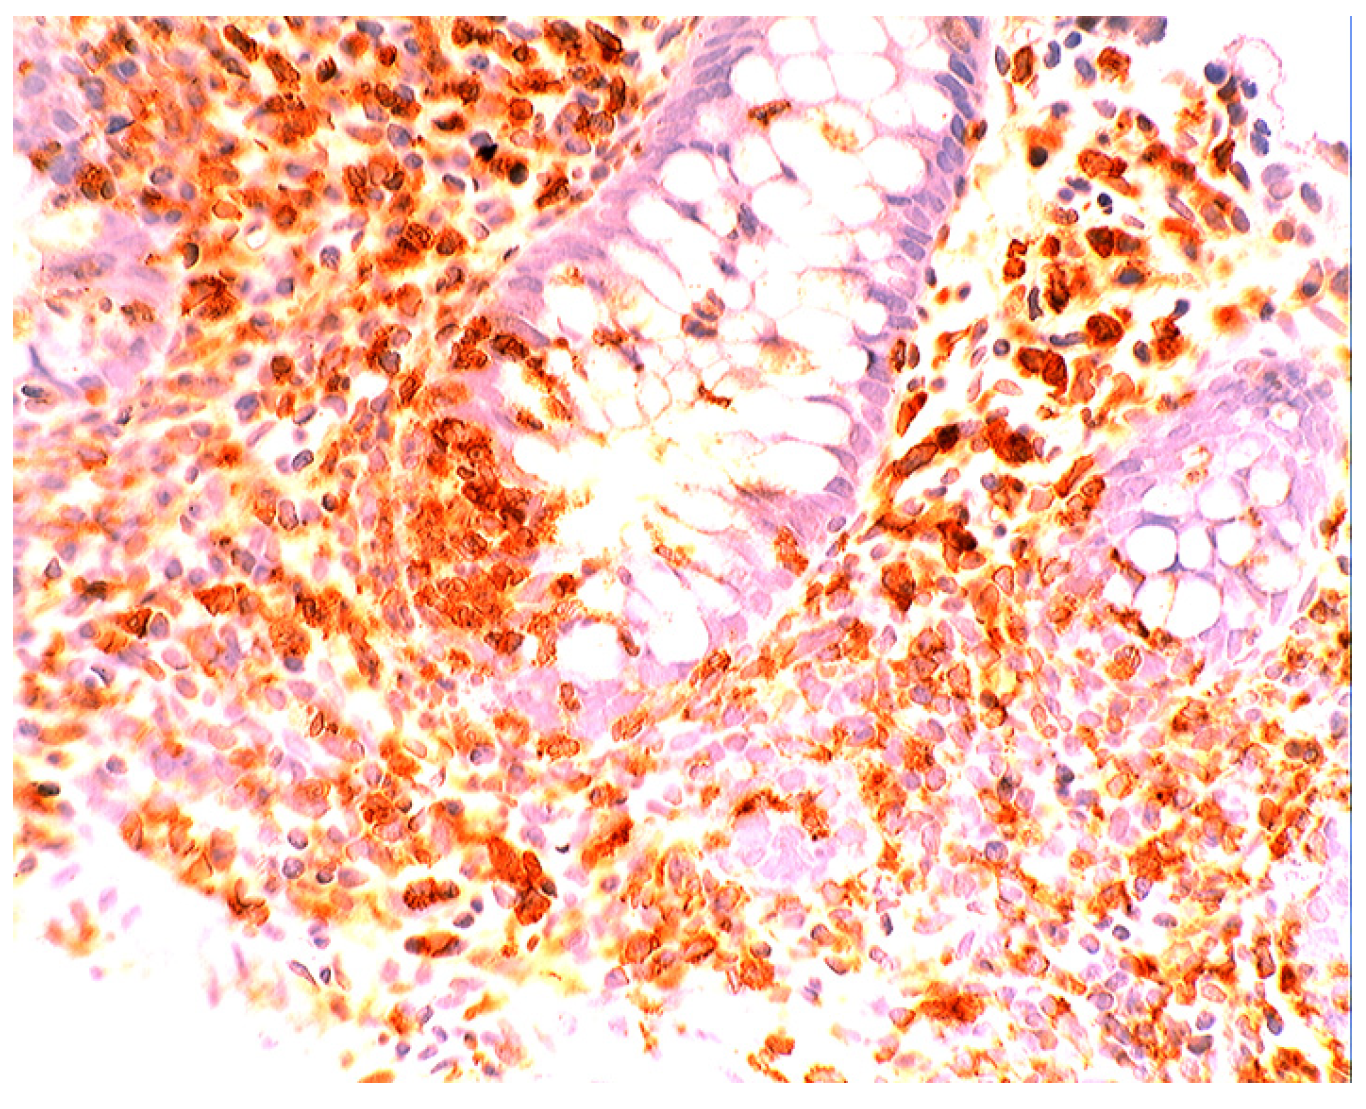

In collagenous colitis lysozyme is up-regulated in the colonic crypts and in metaplastic Paneth cells [9] (Figure 11). In lymphocytic colitis, lysozyme is up-regulated in macrophages underlying the surface epithelium of the lamina propria [9] (Figure 12), as well as in the lower part of the crypts (Figure 13).

Figure 11. Collagenous colitis. Marked lysozyme immunoreactivity in goblet cells in the crypts (lysozyme immunostain, ×40).

Figure 12. Lymphocytic colitis showing marked lysozyme expression, in macrophages in the lamina propria juxtaposing the superficial epithelium (lysozyme immunostain, ×40).